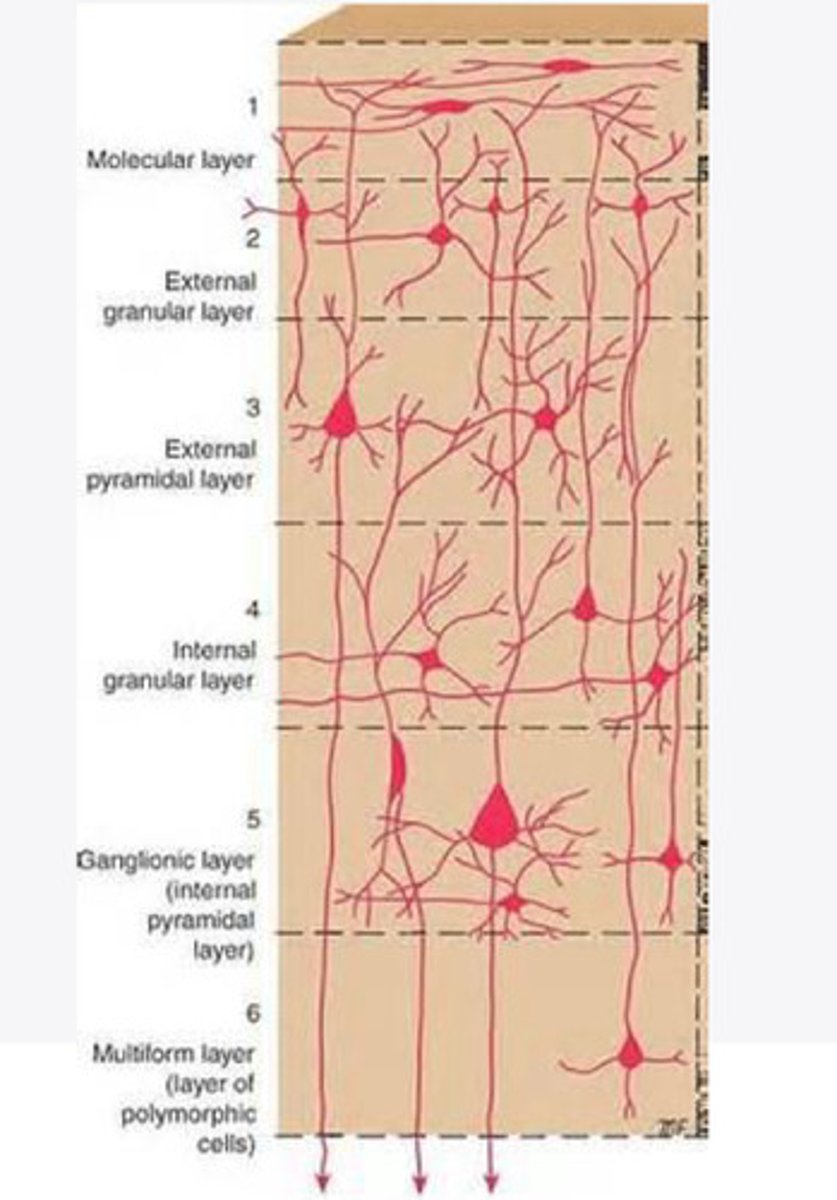

divided into 6 distinct layers, due to varying densities of cell body types within each layer

The cortex of the brain is divided into how many layers? Why is it divided into layers?

Layers of the cortex of the brain pic

2 and 4

What are the layers of the cortex that are associated with input?

3 and 5

What are the layers of the cortex that are associated with output?

molecular layer

What is the name of Layer 1 of the cortex of the brain?

very few cells

Does Layer 1 of the cortex have a lot or few cells?

receives dendrites from internal layers so it may actually function as a coordinating center where layers can communicate action

What does Layer 1 of the cortex do?

1

Every layer sends densities to Layer ____?

1

What layer serves as the "water cooler" of the brain?

external granular layer

What is the name for layer 2 of the cortex of the brain?

receives input from other cortical regions

What is the function of Layer 2 of the Cortex of the brain?

Stellate

What type of cells (stellate/pyramidal) would be most concentrated in Layer 2?

external pyramidal layer

What is the name for layer 3 of the cortex of the brain?

sends output to the other cortical layers

What is the function of Layer 3 of the cortex of the brain?

pyramidal

What type of cells (stellate/pyramidal) would be most concentrated in Layer 3 of the brain?

Layers 2 and 3

What layers are associated with association and commissural fibers?

Layer 3 - axons of cell bodies

Layer 2 - synapse into target areas in Layer 2

What part of the axons is in Layer 2/ in layer 3?

Layer 3 - external pyramidal layer

All axonal cel bodies for association and commissural fibers lie within what layer of the Cortex of the brain?

internal granular

** or called the striate cortex because it is so thick that you can see a line through this layer even in unstrained brain slides

What is the name for the 4th layer of the cortex of the brain?

receives input from the thalamus, geniculocortical layer, and other brainstem areas

What is the function for the 4th layer of the Cortex of the brain?

very thick within the vision, auditory, and somatosensory areas

Is Layer 4 thick or thin within SENSORY areas of the cortex?

Internal pyramidal

What is the name for Layer 5 of the cortex of the brain?

sends axons to the brainstem (corticobulbar) and spinal cord (corticospinal)

What is the function of Layer 5 of the cortex of the brain?

in motor areas of the cortex?

Where is layer 5 very thick in the brain?

the frontal lobe -- very motor heavy

What lobe of the brain will have a thick layer 5 of the cortex of the brain?

the multiform layer

What is the name of layer 6 of the cortex of the brain?

-sends axons back to the thalamus through corticogeniculate fibers

-modulates what information the thalamus sends to the cortex to control the strength of the signal received and modulate what you pay attention to

What is the function of layer 6 of the cortex of the brain?

no

Is layer 6 a motor layer?